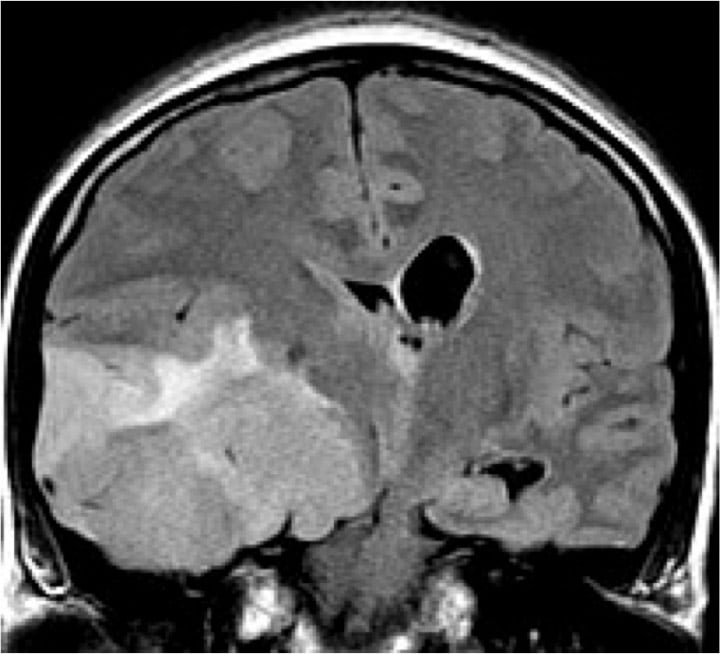

- Brain and spine tumors

- Aneurysms, AVMs and other vascular malformations